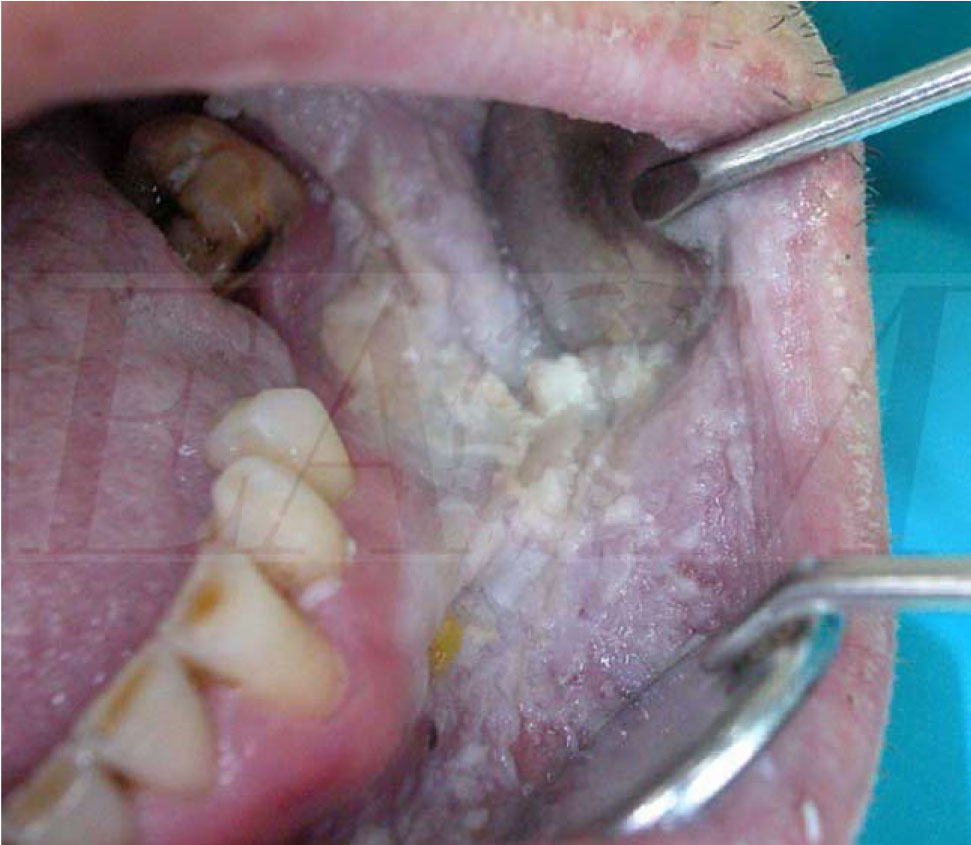

Oral White Sponge Nevus White sponge nevus (wsn) is an uncommon, hereditary benign keratinization defect that primarily affects the oral mucosa and occasionally, though rarely, the skin or other mucosal sites, such as the nose, esophagus and Most commonly white sponge naevus is misdiagnosed as oral candidiasis (thrush) but this can be excluded on. The surface of the plaque is thick,. White sponge nevus (wsn) is an uncommon, hereditary benign keratinization defect that primarily affects the oral mucosa and occasionally, though rarely, the skin or other mucosal sites, such as the nose, esophagus and Familial white folded mucosal dysplasia, leukoderma exfoliativum mucosae oris, hereditary leukokeratosis. White sponge nevus is an autosomal dominant skin disorder characterized by white, irregular, diffuse plaques mainly. White sponge nevus is a rare hereditary mucosal disorder characterized by asymptomatic spongy white plaques that affect oral mucosa and less. White sponge nevus (wsn) is an interesting hereditary oral mucosal disorder that commonly manifests as bilaterally symmetrical, thickened.

Figure 1 from A Case of Nonhereditary White Sponge Nevus in the Oral Oral White Sponge Nevus The surface of the plaque is thick,. Familial white folded mucosal dysplasia, leukoderma exfoliativum mucosae oris, hereditary leukokeratosis. White sponge nevus is a rare hereditary mucosal disorder characterized by asymptomatic spongy white plaques that affect oral mucosa and less. Most commonly white sponge naevus is misdiagnosed as oral candidiasis (thrush) but this can be excluded on. White sponge nevus is. Oral White Sponge Nevus.

Figure 1 from A Rare Clinical Case of Oral White Sponge Nevus and the Oral White Sponge Nevus White sponge nevus is a rare hereditary mucosal disorder characterized by asymptomatic spongy white plaques that affect oral mucosa and less. White sponge nevus is an autosomal dominant skin disorder characterized by white, irregular, diffuse plaques mainly. White sponge nevus (wsn) is an interesting hereditary oral mucosal disorder that commonly manifests as bilaterally symmetrical, thickened. Familial white folded mucosal dysplasia,. Oral White Sponge Nevus.